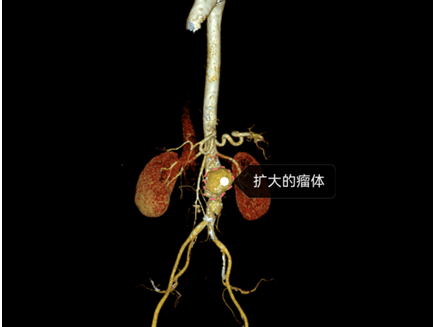

主动脉CT血管造影检查结果是

腹主动脉夹层动脉瘤

直径已达到4.45厘米

图片